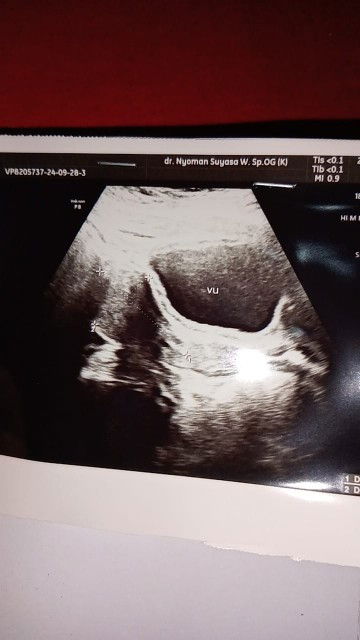

Nanya dong bun ,saya 2 minggu yg lalu tespek posituf terus saking penasarannya usg lah saya ,nah terus kata dokter belum terliat kantong janinnya nanti balolik lagi 2 minggu (itu paling cepat paling lambat sebulan ).. ini setelah 2 minggu di tespek kok negatif kalau keguguran pasti kluar flek atau darah ,nah sedangkan saya ini keluar flek gak ada apalagi darah .. tolong bund aku bingunh + overthinking #Sharing_dong_Bund #baru